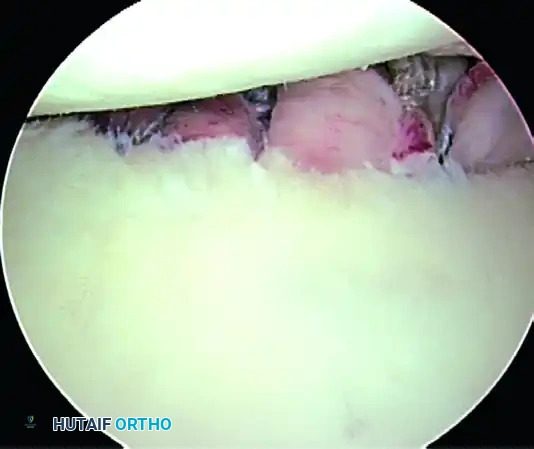

1. Capsulolabral Mobilization and Glenoid Preparation

The most common cause of failure in Bankart repair is inadequate mobilization of the capsulolabral complex.

While visualizing from the anterosuperior portal, use an arthroscopic elevator or radiofrequency wand to meticulously free the capsule down to the 6-o’clock position. You must release the tissue until the underlying red muscle belly of the subscapularis is clearly visible. This complete release is mandatory to allow the inferior capsule to be shifted superiorly without tension.

💡 CLINICAL PEARL: The Biological Bed

Soft tissue healing requires a robust vascular response. Use an arthroscopic rasp or motorized burr to abrade the anterior glenoid neck down to bleeding cancellous bone. Do not over-resect the bone, as preserving the cortical edge is necessary for secure anchor purchase.

A, Abrasion of glenoid neck and capsular release to allow advancement of capsulolabral complex superiorly and laterally to restore anatomy and physiological tension.